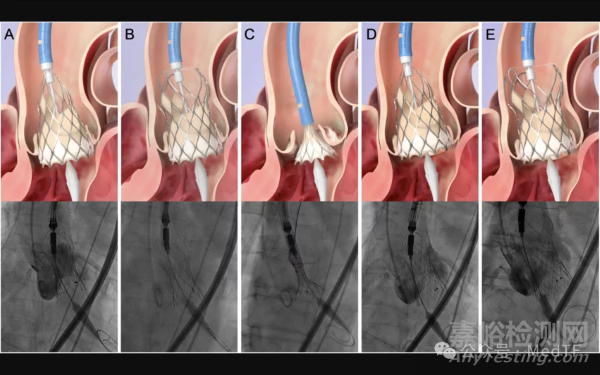

啟明醫(yī)療在《American Journal of Cardiology》發(fā)表全球首個(gè)100%完全釋放后可回收TAVR---Venus-PowerX 的首次人體研究,Venus-PowerX TAVR在完全釋放后仍可回收和重新定位,早期安全性和臨床結(jié)果令人鼓舞。

此外,Venus-PowerX采用線控技術(shù),在瓣膜100%完全釋放后,仍可進(jìn)行回收,較常規(guī)釋放方式更具安全性。同時(shí),該產(chǎn)品的輸送系統(tǒng)采用全新鞘管設(shè)計(jì),優(yōu)化了柔順性及過弓性。瓣架更為精簡,在保證徑向支撐力的同時(shí),三個(gè)”V”口為冠脈介入預(yù)留了通路。